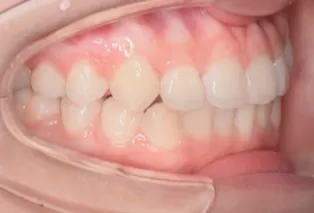

Intraoral photos